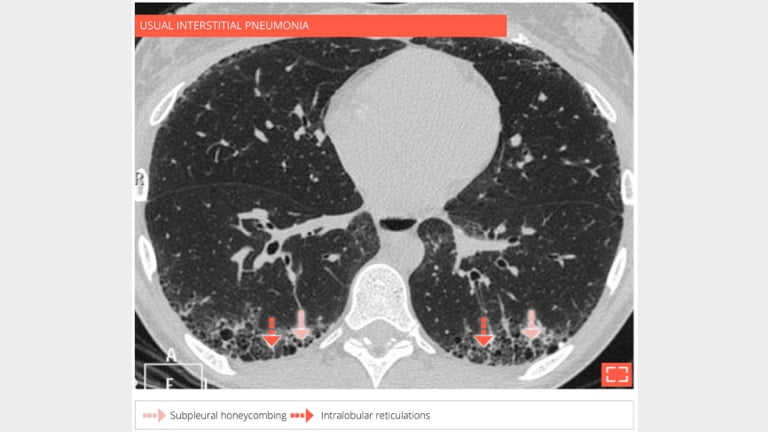

69-year-old man with usual interstitial pneumonia. Subpleural honey combing is associated with reticular pattern.

3. Honeycombing

honey-3

Sagittal reformation in the same patient showing the preferential subpleural and basal distribution.